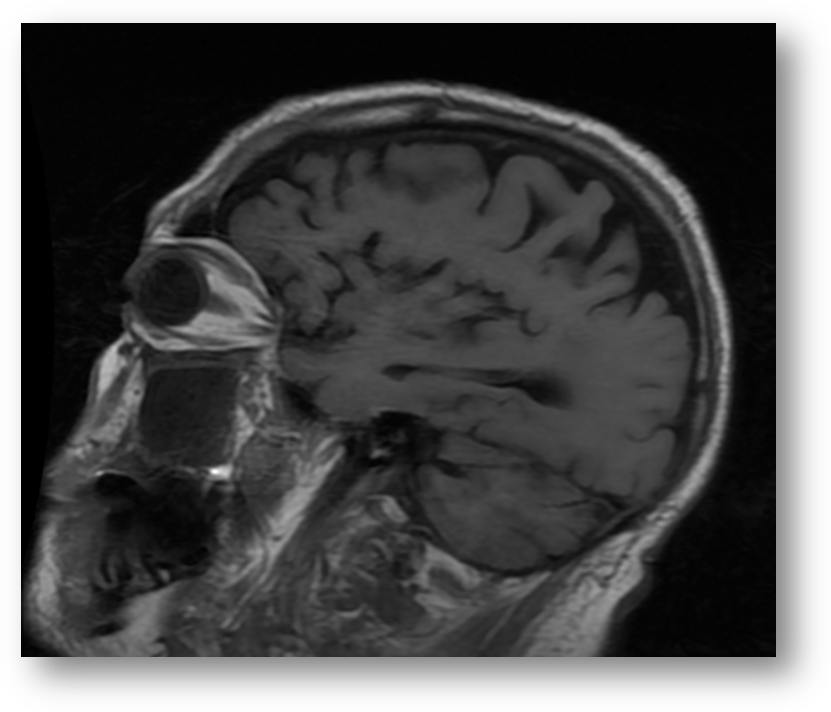

Refer to caption

Figure 2: T1 FLAIR. Sagittal section. Note the hyperintensity of orbital fat, and the hypointensity of vitreous and cerebrospinal fluid. Hyperintensity of fat and hypointensity of water are radiologic characteristics of T1 weighted imaging.

Fluid attenuated inversion recovery (FLAIR) is useful in the diagnosis of certain pathologies such as periventricular white-matter lesion in multiple sclerosis. FLAIR can be T1 or T2 weighted. Figure (2) shows a sagittal section of a T1 FLAIR brain image, and Figure (3) shows a T2 FLAIR brain image.